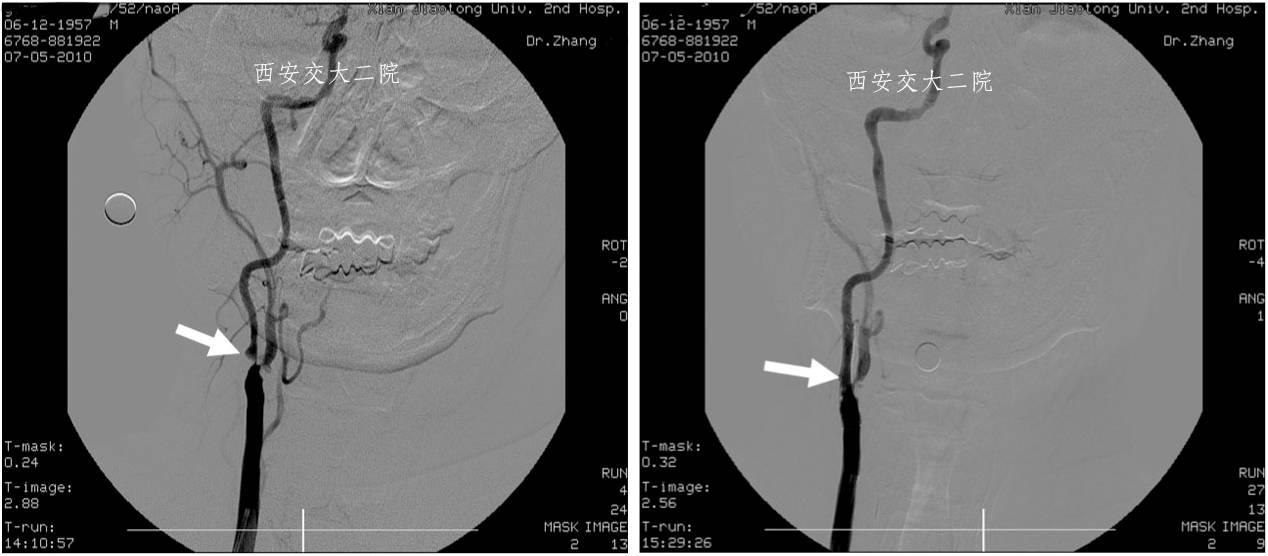

Case 1 颈内动脉狭窄支架成形术(2009年)

》男,52岁,发作性左侧肢体无力2周,右ICA开口狭窄支架后。

Case 2 颈内动脉眼动脉段狭窄(2010年)

》女,51岁,左侧肢体无力1月,加重20天,DSA示右侧颈内动脉眼动脉段狭窄80%。